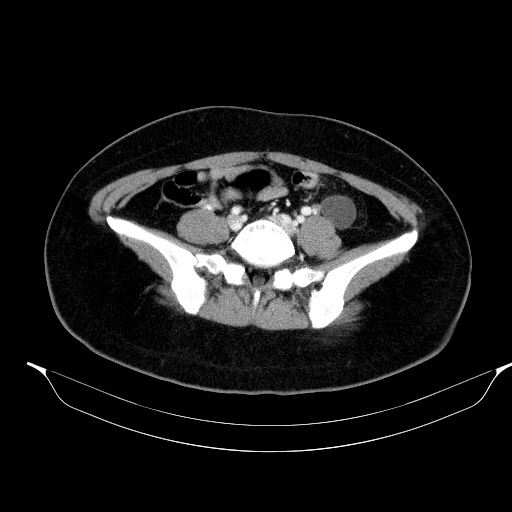

관상면 영상에서 해당 병변은 확실히 Lt. adnexal region의 병변입니다. 여기에 더해 좌측 tube가 함께 두꺼워져 있습니다. 이렇게 tubal thickening이 있으면서 주변에 염증반응이나 조영증강소견이 동반되지 않는 경우는 ovary torsion의 가능성을 배제할 수 없습니다.

환자는 대학병원으로 전원해서 수술 후 torsion 소견이 확인되었으며, Lt. adnexal region의 병변의 정체는 조직검사를 했으나 아직 결과가 나오지는 않았다고 합니다.